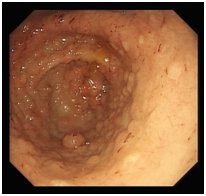

With an iron deficiency anaemia and a concern for an occult GI bleed, endoscopy was performed that showed grossly abnormal, thickened gastric folds in the body and multiple polypoid lesions in the antrum with scattered blood throughout (Figures 3) (Figure 4).

Figure 3Polypoid lesions in the antrum.